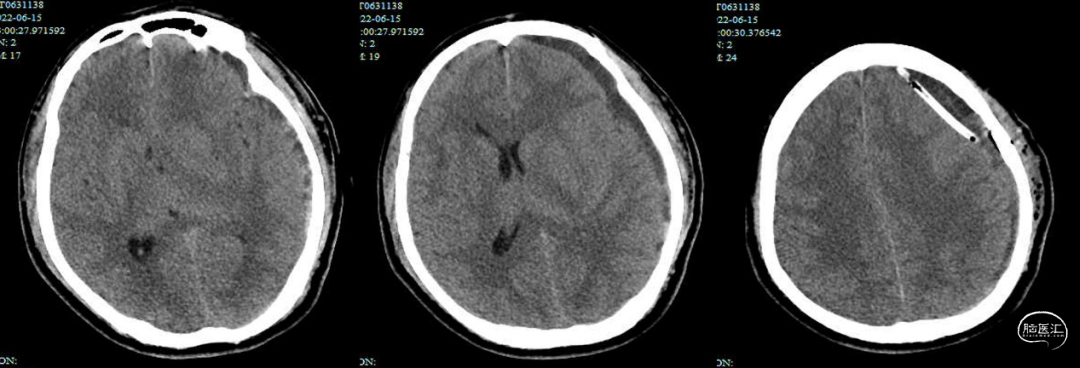

患者22天前因头晕伴恶心呕吐就诊于当地医院,无明确外伤史,入院血压252/160mmHg,头颅CT未见明显异常(图1)。以“高血压急症”住院治疗。入院2天后复查头颅CT检查示左侧特发性急性硬膜下血肿(图2)。6天前(入院后半月)因头晕明显加重,再次复查头颅CT,示左侧亚急性硬膜下血肿,脑疝形成(图3)。在当地医院急诊行左侧硬膜下血肿钻孔引流术”,术程顺利,术后1天复查头颅CT示左侧血肿较术前减少(图4)。术后患者症状改善,术后6天下床活动后出现意识下降、言语含糊,头颅CT提示左侧硬膜下血肿复发。遂转至我院,查头颅CT示左侧硬膜下血肿术后,左侧额顶颞枕部硬膜下血肿;中线结构右偏明显,局部脑疝形成(图5)。

急诊完善相关检验检查,诊断考虑血肿术后复发、脑疝形成,排除禁忌后,于2022-06-20急诊全麻下行“开颅左侧硬膜下血肿清除术及去骨瓣减压术”。术后复查头颅CT提示:左侧硬膜下血肿清除+引流术后,左侧额顶颞枕部硬膜下血肿伴积气;较前2022-06-20中线右偏程度减轻(图6)。术后患者昏迷,转入脑重症医学科予以监护对症治疗,期间患者病情趋稳、意识有所好转,脱机拔管后于6月24日转入普通病房,GCS评分E4V2M4。复查头颅CT(2022-06-24)示:较前2022-06-21硬膜下积血稍增多,中线右偏加重(图7)。6月26日患者再次意识出现下降,浅昏迷,GCS评分E1V1M3,左侧瞳孔光反应迟钝。